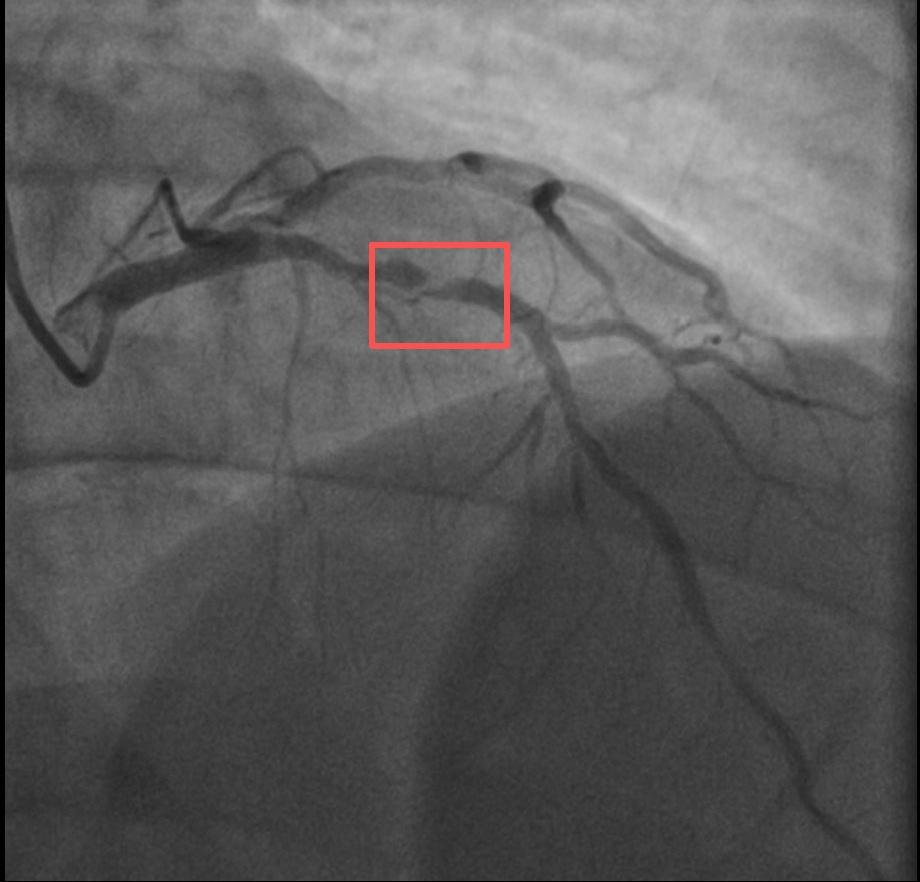

38岁爸爸打10分钟羽毛 球突然心梗!同一天另一位爬山后被送医,医生严肃提醒:运动可当不了万能通行证,这些细节可能致命! 那天急诊室里,一下子就送来了两位38岁的爸爸。其中一位是陪着孩子打了大概10分钟羽毛球,正玩得热闹时,突然捂着胸口疼得直不起腰,直接倒在了地上。明明一年前就查出冠脉有60%的狭窄,却一直没好好治疗,总想着靠运动能把血管养回来。另一位则是周末带孩子去爬山,爬完山后胸口像压了块大石头似的疼,被家人紧急送到医院,一检查才发现,他的血糖和血脂早就高得离谱。 医生看着这两个病例,总结出三个最容易要命的“导火索”:第一,突然做太剧烈的运动,血管里的斑块可能会被“冲”破;第二,本身血管就有狭窄,运动时心脏要跳得更快,供血跟不上就会出问题;第三,天冷的时候,血管一收缩,也容易引发危险。更让人担心的是,很多人平时就踩了这些“坑”——熬了大夜还硬要去运动,感冒还没好利索就急着动,或者好几天不运动,周末突然猛练一场。 记住四个“保命”的字:循序渐进!运动的时候,要是还能完整说一句话,那强度就算安全的。要是感觉胸口闷得慌,或者左边肩膀也跟着疼,赶紧停下来别动。这两位爸爸拿自己的命换来的教训:孩子要的是一个能健健康康陪他长大的爸爸,而不是朋友圈里晒运动打卡的“达人”。 快转发给那个总说“我身体好着呢,没事”的朋友!你身边有没有那种总爱说“我能行,运动就没事”的“运动狂人”?他们的故事说不定就能让更多人明白这个道理——健康活着,比什么都重要啊!